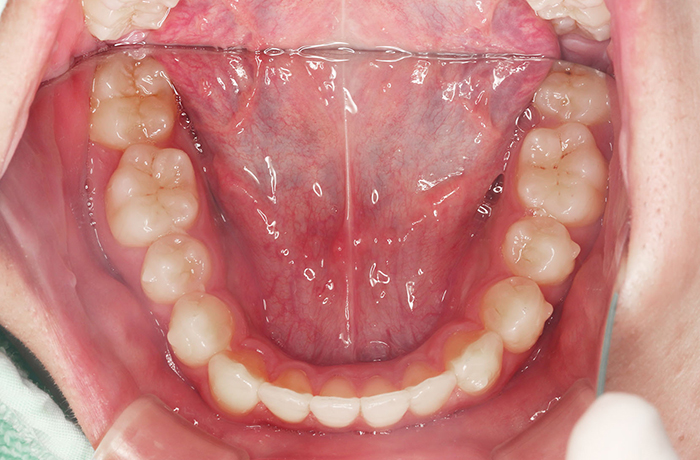

after

年齢 34歳

性別 男性

治療名称 マウスピース型カスタムメイド矯正歯科装置(インビザライン)・コンプリヘンシブパッケージ(フルパッケージ)

総額治療費用 770,000円(税込) 金額備考 検査・診断料33,000円含む

治療期間 8か月 通院頻度など 40日ごと

その他治療に関する情報 1枚につき10日装着を指示しました。

治療内容

患者の症状 上顎前歯の凸凹

治療方法 非抜歯で、マウスピース型カスタムメイド矯正歯科装置による矯正

治療結果 歯並び、咬み合わせが良くなりました。

その他治療に関する情報 歯並びをより良くするために追加でアライナーを発注しました。

治療を行う上での注意点

リスク/副作用 スペース不足を解消するために歯と歯の間をわずかに削合しました。